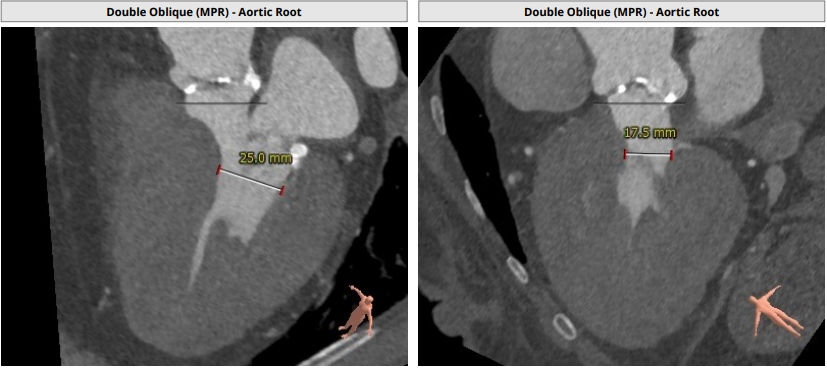

CT报告评估:

Annulus:24.4mm,LVOT:22.6mm,Asc.Ao:43.4mm,STJ:30.7mm。

LCA:10.7mm,RCA:15.0mm。

瓣环结构及钙化情况:患者为TYPE 1型二叶瓣,瓣环及左室流出道呈上宽下窄型结构,钙化积分为529,主要集中于无冠窦,从基底部开始延申至左右融合处及无冠窦游离缘,整体窦部空间合适。

心室情况:升主动脉增宽,心脏角度59°,严重心肌增厚,心室腔小。